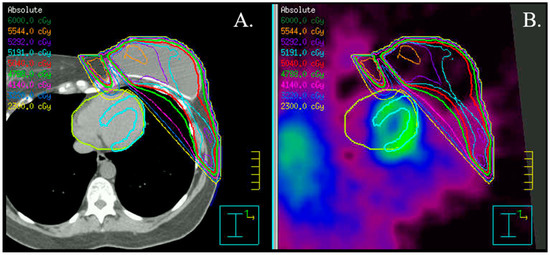

- Dreyfuss, A.D.; Goia, D.; Shoniyozov, K.; Shewale, S.V.; Velalopoulou, A.; Mazzoni, S.; Avgousti, H.; Metzler, S.D.; Bravo, P.E.; Feigenberg, S.J.; et al. A Novel Mouse Model of Radiation-Induced Cardiac Injury Reveals Biological and Radiological Biomarkers of Cardiac Dysfunction with Potential Clinical Relevance. Clin. Cancer Res. 2021, 27, 2266–2276. [Google Scholar] [CrossRef]